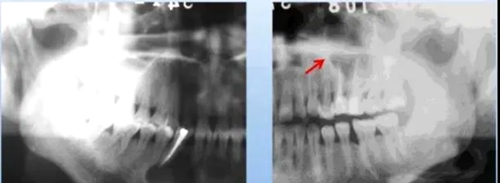

(1) 致密性骨炎

臨床表現(xiàn):好發(fā)于年青人,常見下頜第一磨牙,常有大齲壞,無(wú)癥狀。

X線表現(xiàn):骨小粱增粗、變密,骨髓腔變窄、消失;

硬化區(qū)與正常組織無(wú)明顯分界;

牙周膜間隙增寬,根尖無(wú)增粗。

(2) 牙骨質(zhì)增生

臨床表現(xiàn):多無(wú)癥狀,發(fā)現(xiàn)于拔牙困難或X片

X線表現(xiàn):牙根粗大;牙周膜間隙變窄或消失。

(3) 牙骨質(zhì)結(jié)構(gòu)不良

臨床表現(xiàn):好發(fā)于20歲以上女性,好發(fā)于下頜切牙的根尖部位。

X線表現(xiàn):

早期:邊界清楚、累及多個(gè)牙

第二期:骨質(zhì)破壞區(qū)可見點(diǎn)狀或團(tuán)狀鈣化影

第三期:根尖區(qū)界限清楚、高致密度鈣化影,牙周膜間隙及骨硬板清楚。